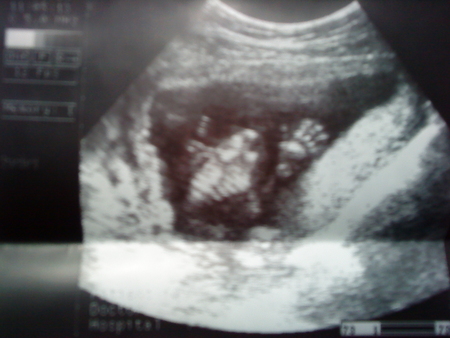

Кста так прикольно сфотографировали маленькую ладошку, масенькие растопыренные пять пальчиков